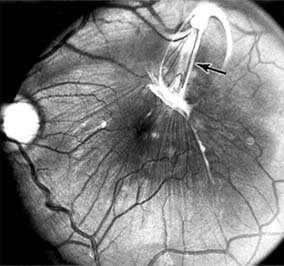

Figure 10-7

Figure 10-7: Late fluorescein leakage from macular subretinal neovascularization in a patient with presumed ocular histoplasmosis syndrome.